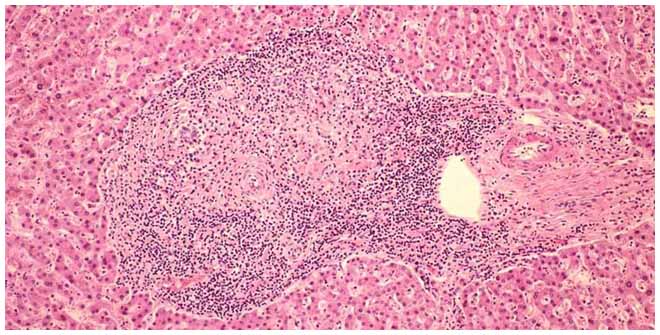

- Биопсия печени-это исследование ее ткани под микроскопом. Добывается материал для исследований при помощи ультратонкой иглы, под контролем УЗИ. Это исследование ставит самый точный анализ, подтверждая или полностью исключая наличие опухоли;

Спустя несколько лет начинается запущенная, а следовательно опасная стадия первичной формы билиарного цирроза. Портальные тракты замещаются рубцовой тканью. Возникают некрозы паренхимы. Выявляются очаги воспаления разной степени активности. На этом этапе усиливаются все имеющие место симптомы и начинают появляться явные признаки печеночной недостаточности(появление сосудистых звездочек, асцит, энцефалопатия). Кроме того, появляются следующие изменения: